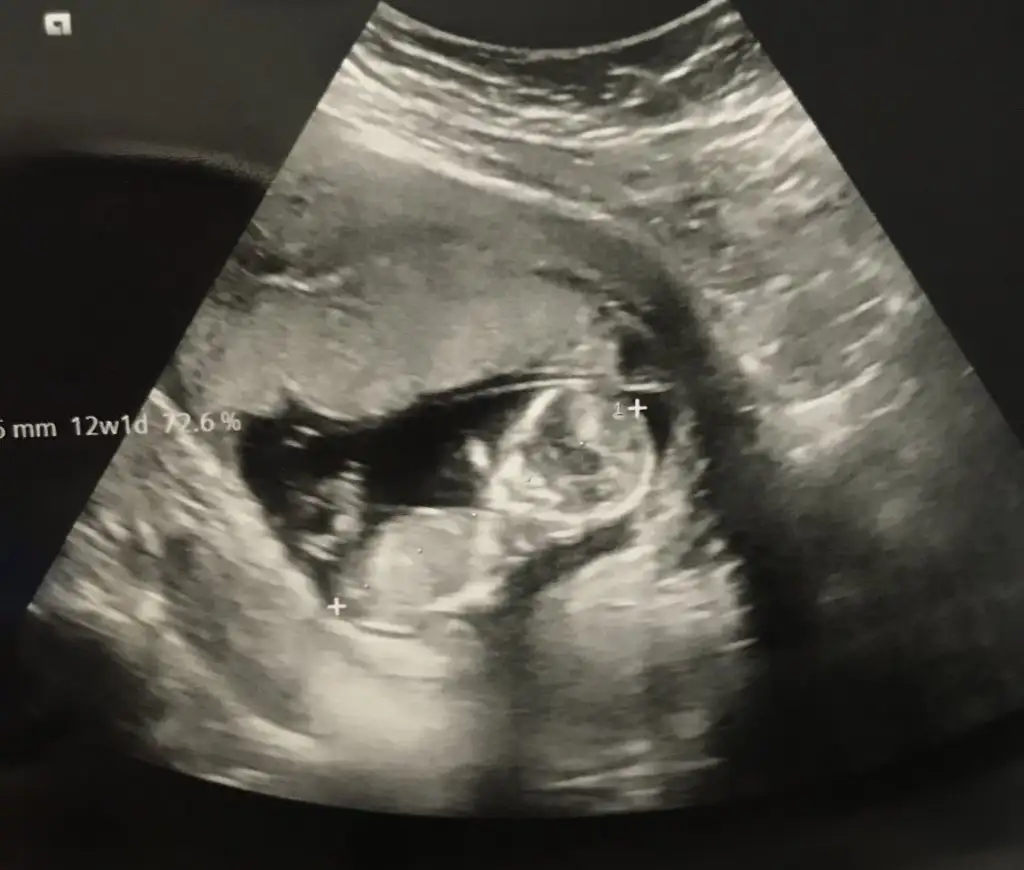

banada tahmin yapabilir misiniz 12haftalik![]()

Bence senin bebiş kız canım bende az cok anlıyorum tahminlerim de cogu zaman tutuyor

Erkek gibi sanki eninde olamadim çok karanlık nubu sanki biraz bir diklik var umarım u nubturIkra meyra 12+1 iz bize de tahmin de bulunabilir misiniz![]()